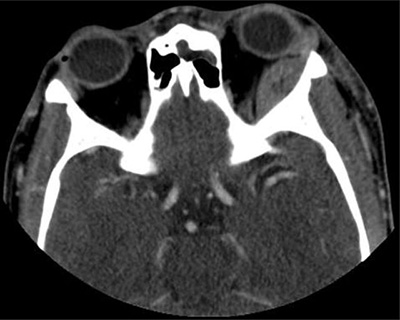

Figure 1

Axial contrast-enhanced CT: A biconcave lesion lining the superolateral left orbital wall.

A 19-year-old male patient with the homozygous sickle cell trait was admitted to the hospital due to a sickle cell crisis. His main complaint was unbearable pain in the extremities. The patient’s history was remarkable for multiple previous admissions for sickle cell crises. During his admission he developed a swollen left eye, with discrete ptosis of the upper eyelid and minimal exophthalmia. There were no visual disturbances and eye movement was unimpaired. A contrast-enhanced computed tomography (CT) of the orbits showed a lens shaped extraconal mass lining the lateral wall of the left orbit (Figure 1). The lesion measured 3.1 × 1.2 cm with high attenuation due to enhancement or spontaneously dense compounds. The underlying frontal and sphenoid bones were unremarkable. The patient was referred for MRI the same day for further work-up. The lesion was markedly hypointense on T2-weighted images with fat suppression (Figure 2A). T1-weighted sequences showed an isointense signal comparable to the adjacent bone (Figure 2B). There was no lesional enhancement after injection of gadolinium and faint perilesional enhancement (Figure 2C). Imaging findings were compatible with an acute subperiosteal orbital hematoma (SOH). Additionally, MRI revealed a new extracranial subperiosteal hematoma lining the external table of the frontal bone on the left side (Figure 2C). This hematoma was less hypointense on T2-weighted images and exhibited more prominent perilesional enhancement. The frontal bone and left greater wing of the sphenoid bone showed discrete bone oedema on T2-weighted images (Figure 2D) and asymmetrical low signal intensity on contrast-enhanced T1-weighted images (Figure 2F), suggesting areas of infarction. The patient received supportive treatment after diagnosis, and the eye swelling diminished spontaneously over time.

Imaging is important for the differential. Our patient received prompt CT and MRI evaluation on the same day. Although the lesion was hyperdense on CT, we could not be sure if this represented blood or contrast enhancement as only contrast-enhanced CT was performed. The signal characteristics on MRI of this nonenhancing lesion combined with the acute clinical presentation were compatible with an acute hematoma, hence the diagnosis of a subperiosteal hematoma. The markedly T2-hypointense signal made a neoplastic lesion less likely.